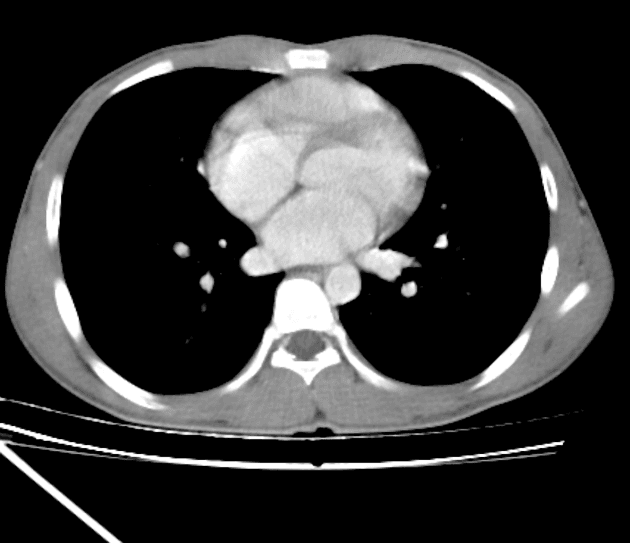

Axial C+ arterial phase

- Tràn khí màng phổi đỉnh bên phải mức độ nhẹ.

- Dịch màng phổi nhỏ bên phải, trong bối cảnh chấn thương, đây nhiều khả năng là tràn máu màng phổi (hemothorax).

- Tràn khí màng phổi bên phải mức độ nhẹ và dịch màng phổi.

- Gãy xương sườn phải các số 10, 11 và 12, nhưng không có đoạn xương chìm (flail segment).

- Xẹp một phần thùy dưới phổi phải, kèm các khoảng chứa khí dạng nang trong nhu mô phổi, đại diện cho các tổn thương rách phổi (lung lacerations).

- Dấu hình cành cây giảm tỷ trọng trong gan, lan từ hõm túi mật đến phân đoạn V, đại diện cho tổn thương rách nhu mô gan/huyết khối nhu mô gan (laceration/parenchymal hematoma).

- Vùng tổn thương tương tự nhưng nhỏ hơn nằm liền kề dây chằng liềm.

- Không có dấu hiệu tổn thương thận hoặc ruột.